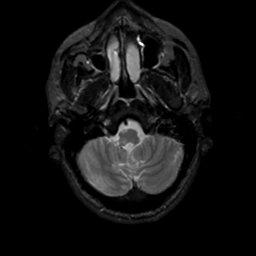

MR Study #7, March 24, 1991 -- Slice #7